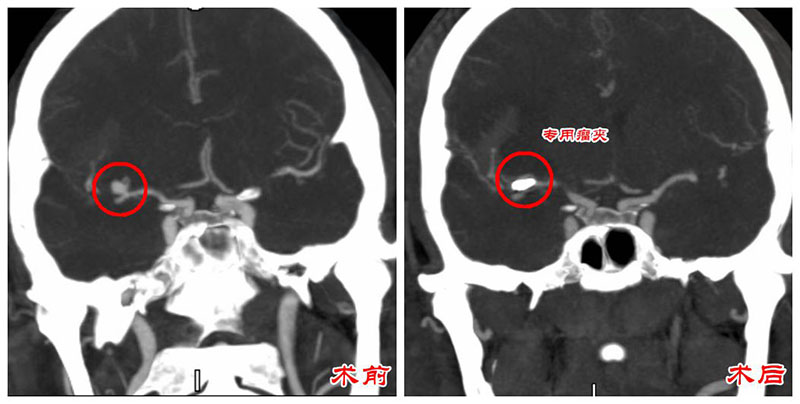

“刚送到急诊科,患者又呕吐了一回,考虑是脑动脉瘤破裂出血后颅内压过高的关系。”接诊的神经外科副主任医师陈思强解释,结合CTA检查,患者为“大脑中动脉瘤破裂伴蛛网膜下腔出血”,性命攸关。

情况危急,急救团队先予以甘露醇、激素降颅压以及气管插管等抢救治疗手段。待颅内压稳定后,神经外科团队在全麻下行“右侧眶外侧入路开颅脑动脉瘤夹闭术、骨瓣复位术”。

手术顺利完成,术后次日,患者神志转清,拔除气管插管,从ICU转回神经外科。因为治疗及时,肖先生目前恢复良好,对答流畅、四肢活动自如。